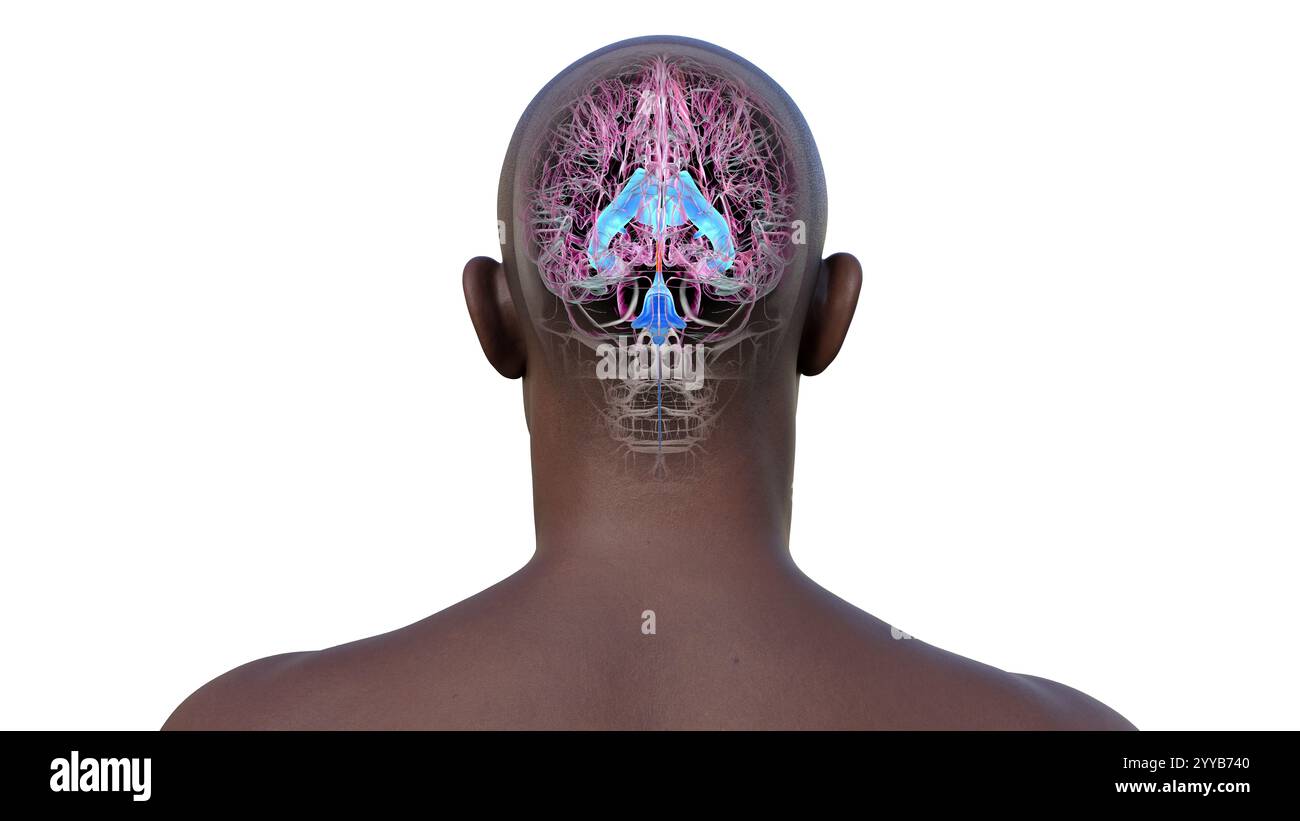

RF2YYB751–Computerdarstellung des cerebralen Aquädukts (orange), eines schmalen Kanals im Mittelhirn, der den dritten und vierten Ventrikel verbindet und den Liquorfluss erleichtert.

RF2YYB74X–Computerdarstellung des cerebralen Aquädukts (orange), eines schmalen Kanals im Mittelhirn, der den dritten und vierten Ventrikel verbindet und den Liquorfluss erleichtert.

RF2YYB75A–Computerdarstellung des cerebralen Aquädukts (orange), eines schmalen Kanals im Mittelhirn, der den dritten und vierten Ventrikel verbindet und den Liquorfluss erleichtert.

RF2YYB754–Computerdarstellung des cerebralen Aquädukts (orange), eines schmalen Kanals im Mittelhirn, der den dritten und vierten Ventrikel verbindet und den Liquorfluss erleichtert.

RF2YYB75B–Computerdarstellung des cerebralen Aquädukts (orange), eines schmalen Kanals im Mittelhirn, der den dritten und vierten Ventrikel verbindet und den Liquorfluss erleichtert.

RF2YYB759–Computerdarstellung des cerebralen Aquädukts (orange), eines schmalen Kanals im Mittelhirn, der den dritten und vierten Ventrikel verbindet und den Liquorfluss erleichtert.

RF2YYB755–Computerdarstellung des cerebralen Aquädukts (orange), eines schmalen Kanals im Mittelhirn, der den dritten und vierten Ventrikel verbindet und den Liquorfluss erleichtert. Rückansicht.

RM2CE564C–. Erkrankungen des Nervensystems . Abb. 43. – Basis der Braix axd Hirnnerven. Sucht nach ihren Hauptabteilungen im Menschen, der Korpora quadrigemina (siehe Abb. 44und 45) oben die Spalte von Sylvius unten, und darunter die Fasermasse der oberen Pedunkles des Kleinhirns und der Pedunculi cerebri (Abb. 46, 47, 48, 49). Seine Kerne (Neuronenzellen) liegen entlang der gesamten Länge des Aquädukts von Sylvius, von seinem frontalen Ursprung fast bis zu seinem kaudalen Ende;5 52 HISTOLOGIE DES ZENTRALNERVENSYSTEMS die Kerne der trochlearen Nerven liegen posteriorly dort, wo der aque-Ductus liegt

RF2YYB752–Computerdarstellung des cerebralen Aquädukts (orange), eines schmalen Kanals im Mittelhirn, der den dritten und vierten Ventrikel verbindet und den Liquorfluss erleichtert. Rückansicht.

RF2YYB75E–Computerdarstellung des cerebralen Aquädukts (orange), eines schmalen Kanals im Mittelhirn, der den dritten und vierten Ventrikel verbindet und den Liquorfluss erleichtert. Ansicht von unten.